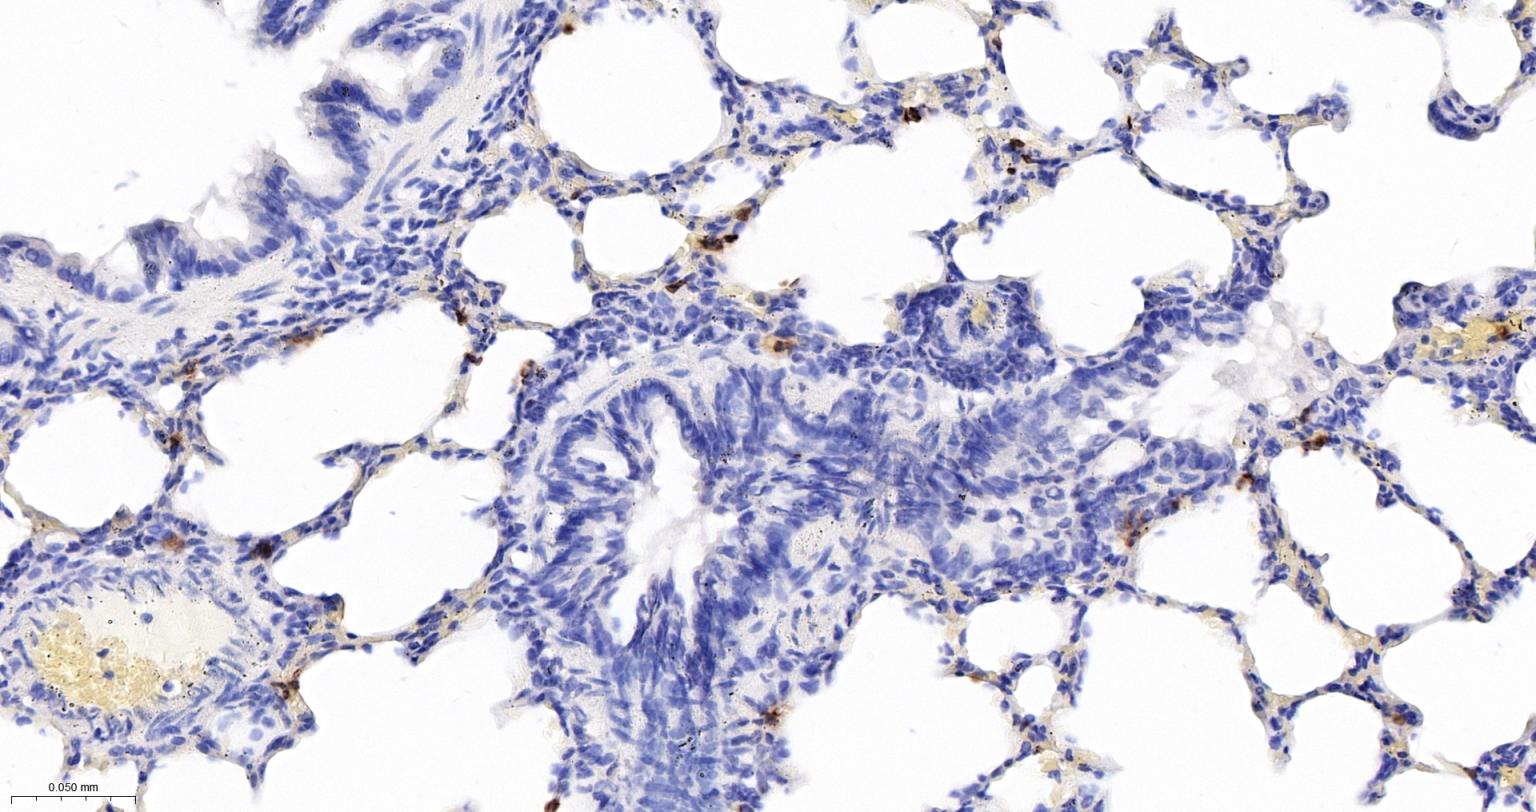

Paraformaldehyde-fixed, paraffin embedded Rat Lung; Antigen retrieval by boiling in sodium citrate buffer (pH6.0) for 15 min; Antibody incubation with S100A8 Monoclonal Antibody, Unconjugated(bsm-61167R) at 1:200 overnight at 4°C, followed by conjugation to the bs-0295G-HRP and DAB (C-0010) staining.